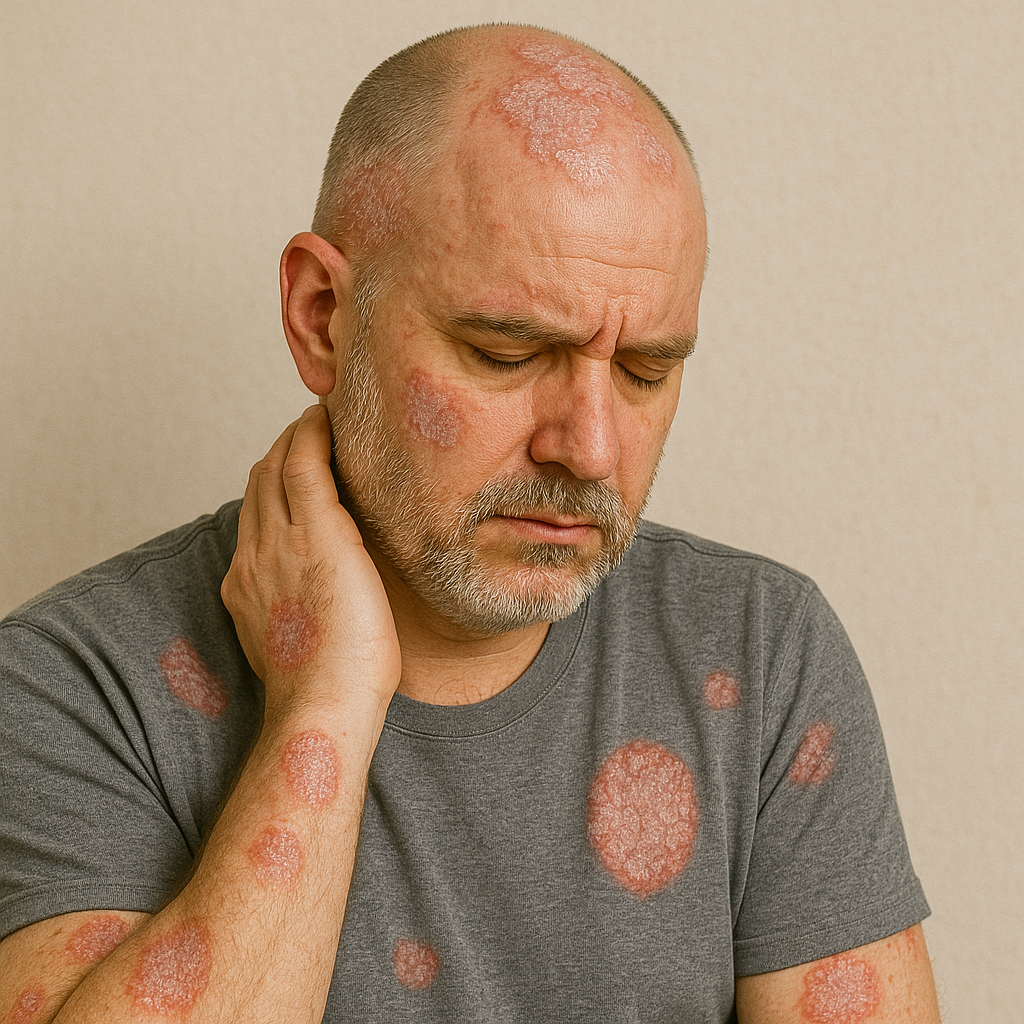

# Skin and Hair